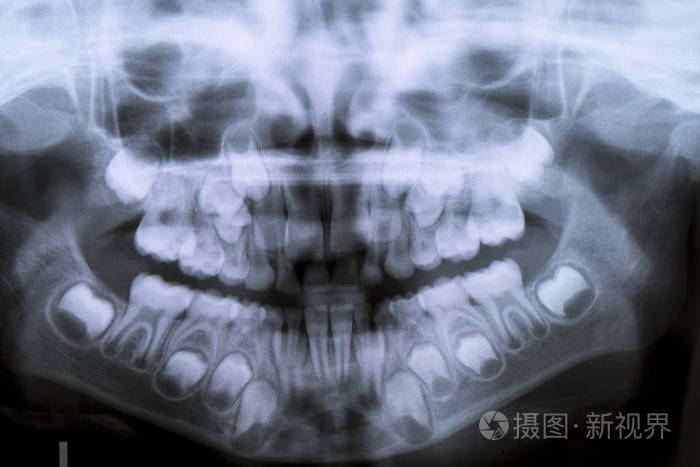

儿童面部x光 牙齿,面部x光

x线片上的一种专用x线机,能显示上腭,鼻腔,下颌骨的结构和全部牙齿

全景牙科 x 射线八岁儿童的问题不松动他的乳牙-持续乳牙